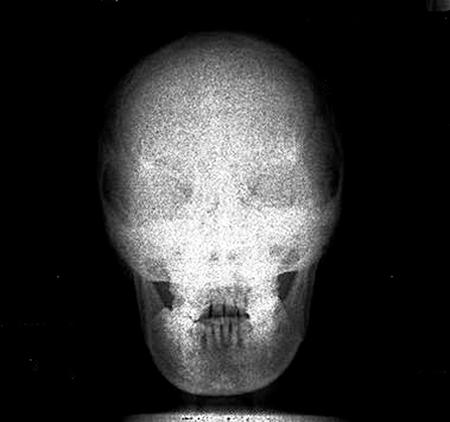

Depending on the type of system being used, the technologist will choose the body part imaged either prior to exposure of the image receptor or after exposure. If the examination room has a PSP housed in the detector in the table or a wall stand, the patient worklist will most likely be in the room’s workstation, which means the technologist may choose the appropriate body part automatically. Always check to make sure the appropriate part has been selected. When using a cassette-based system, the selection of the body part is usually done after exposure and it is imperative that cassettes are kept apart so that the technologist knows which cassette goes with which body part. For example, if a skull examination is to be performed, the technologist would choose “skull” from the workstation menu (Fig. 4.16). Selecting the proper body part and position is important for the proper conversion to take place. Image recognition is accomplished through complex mathematical computer algorithms, and if the improper part and/or position is designated, the image may be processed incorrectly and fail to display properly. For example, if a knee examination is to be performed and the examination selected is for skull, the computer will interpret the exposure for the skull, resulting in improper image display (Fig. 4.17). The resultant image might appear too dark or too light and it might appear grainy or as if it was underexposed. It is not acceptable to select a body part or position other than that being performed simply because it provides a better image. If the proper examination/part selection results in a suboptimal image, then service personnel should be notified of the problem so it can be corrected as soon as possible. Improper menu selections may lead to overexposure of the patient and/or repeated exposure.